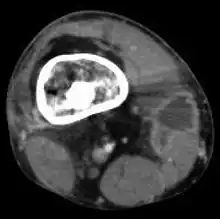

Le scanner

Il permet d'étudier surtout l'extension osseuse dans les formes chroniques (aspect hétérogène) et surtout de détecter la présence d'un séquestre, fragment d'os mort qui agit comme un corps étranger et favorise la persistance des fistules : c'est un élément essentiel de l'indication chirurgicale dans les suppurations persistantes. Il permet également d'étudier les localisations vertébrales et sacro-iliaques.